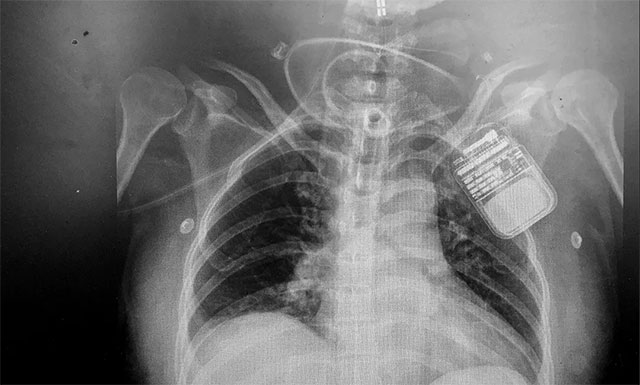

▲ 电刺激器顺利置入患者脊髓上方

脊髓神经电刺激置入术,是通过微创手术将电极置入脊髓上方,以脉冲电流刺激脊髓神经,增加脑血流、脑代谢,而且还能激活脑干网状上行系统,这样不仅能改善脑循环、缩小缺血灶,还能兴奋大脑皮层,促进患者神志清醒。该技术具有微创、可逆,并可依据患者病情需要进行治疗参数的调节,实现个体化定制,同时可有效改善患者全身循环水平等优势,对长期昏迷患者有很好的促醒作用。

在对患者进行严格的术前评估后,2020年2月19日,潘仁龙主任领衔的专家团队对其进行了“脊髓神经电刺激置入术”,手术顺利完成。术后,根据张女士的具体病情,对刺激参数进了调节,之后她意识情况较前明显改善,眼睛已经可以睁开,眼球可随人影和声音移动,四肢肌张力也逐渐恢复正常,僵硬的肢体也变得柔软,情感反应也更加丰富,随着脊髓神经电刺激的持续调节治疗,张女士的意识情况将会进一步得到恢复。